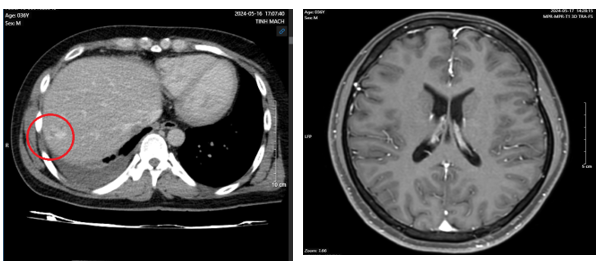

- Chụp cắt lớp vi tính lồng ngực sau điều trị 10 tháng: Nhu mô thùy trên sát rãnh liên thùy lớn có tổn thương dạng hang chứa khí kích thước 18x13mm, thành dày, có xơ hóa lân cận. Nhu mô phổi còn lại có vài nốt đặc, nốt lớn nhất đường kính 6mm. Phổi trái có vài nốt đặc bờ đều đường kính 5 mm.

Hình 3: Hình ảnh chụp cắt lớp vi tính lồng ngực sau điều trị 10 tháng: các nốt tổn thương gần hết và không có tràn dịch màng phổi

- Chụp cắt lớp vi tính ổ bụng: Nốt đặc xương thân -cánh trái xương cùng kích thước 15×8 mm và xương cánh chậu trái kích thước 13×9 mm. Hình ảnh theo dõi u máu gan phải/ gan nhiễm mỡ

Hình 4: hình ảnh chụp cắt lớp vi tính ổ bụng sau điều trị 10 tháng không có tổn thương nghi ngờ thứ phát